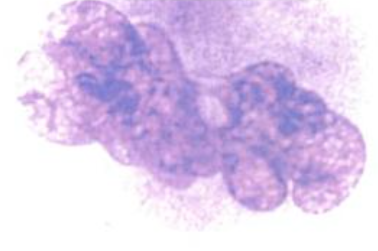

Megacarioblasto Mide de 10 a 15 micras, la relación núcleo:citoplasma está bastante aumentada, núcleo con basofilia baja, tiene unos 6 nucleolos, el citoplasma es escaso y no tiene gránulos (Rodak, 2004). Se encuentra en la médula ósea, se parece a otros blastos, por lo que es difícil lograr diferenciarla. En este estado puede sufrir varia divisiones nucleares y aumentar su citoplasma hasta unas 50 micras (Rodak, 2004).

Fuente: Rodak, E. (2004). Hematología: Fundamentos y Aplicaciones. (2da ed.). Madrid, España: Editorial Médica Promegacariocito Se ubica en la médula ósea, es la maduración del megacarioblasto y llega a medir hasta 80 micras. Posee aparato de Golgi y ya hay gránulos alfa, densos y lisosómicos formados en todo el citoplasma (Rodak, 2004).

Fuente: Rodak, E. (2004). Hematología: Fundamentos y Aplicaciones. (2da ed.). Madrid, España: Editorial Médica Megacariocito La relación núcleo:citoplasma ha disminuido, la basofilia del núcleo está aumentada, es céntrico y está lobulado. El citoplasma es acidófilo (Rodak, 2004).

Fuente: Rodak, E. (2004). Hematología: Fundamentos y Aplicaciones. (2da ed.). Madrid, España: Editorial Médica El megacariocito libera segmentos citoplasmáticos a través de fenestraciones del epitelio de los vasos, a esto se le llama brote plaquetario (Rodak, 2004).